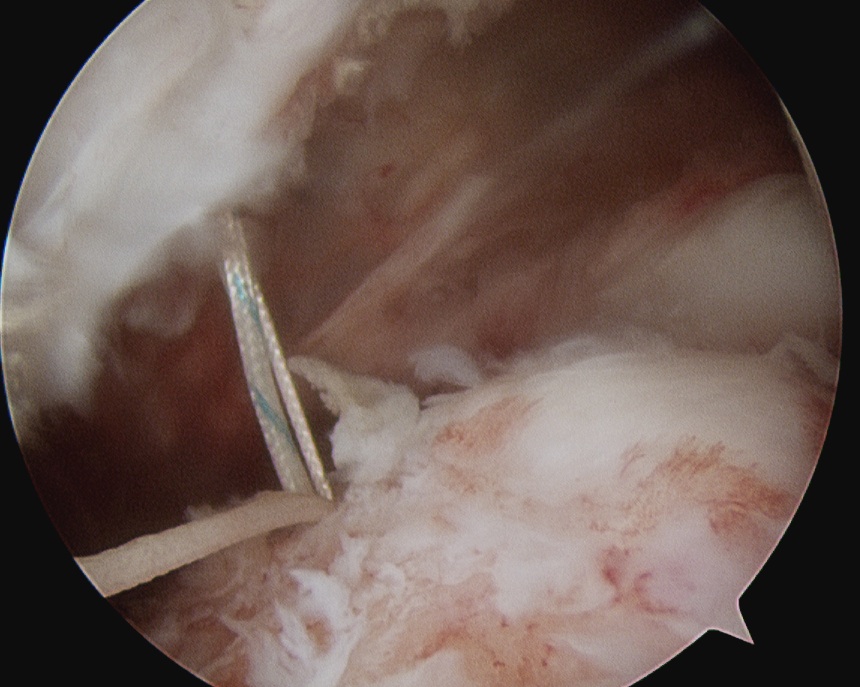

Prepare footprint

- debride

- insert anchors (retract port of Wilminton into subacromial space)

- pass sutures with suture passer